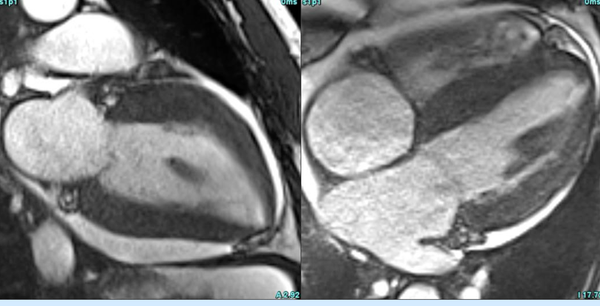

Cardiac MRI is a useful tool to diagnose amyloidosis. T1 mapping has become a mainstay, both native and ECV measurements. ECV measurement can now help quantify the amyloidosis burden and may help guide treatment based on how the ECV responds to specific treatment measures.

It is not just cardiac MRI and cardiac CT that give us clues to a cardiac pathology. We should look at the heart on any cross-sectional thoracic study.